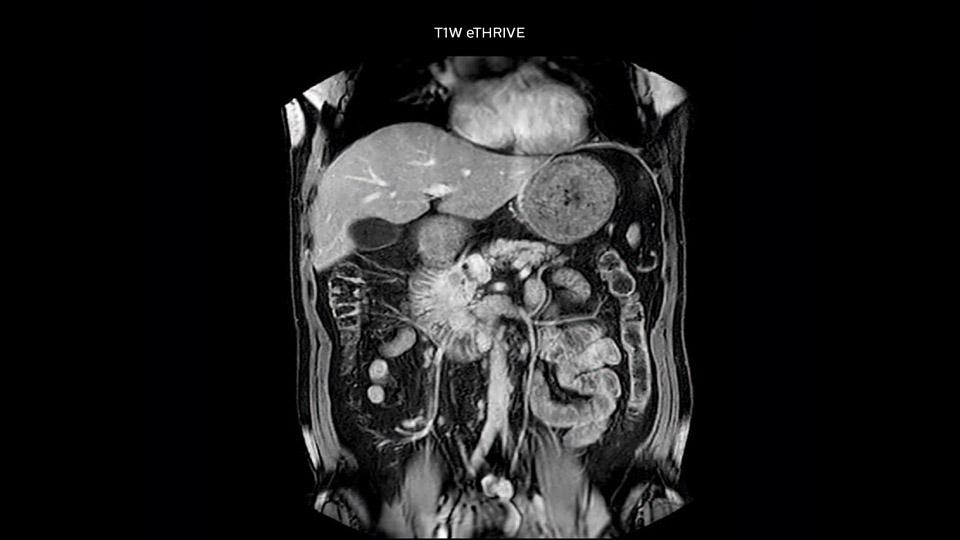

Comparison of liver MRI with and without MultiVane XD motion correction

In this example the image quality of the MultiVane XD images is evidently better than in the images without MultiVane XD. Ingenia 1.5T with dS Torso coil solution.

“We include mDIXON for the dynamic sequences because of the robust and homogeneous fat suppression we get with that. We had been using eTHRIVE, but we are now quite happy with mDIXON. Sometimes we use a medication to calm the bowels, to further improve the image quality.”